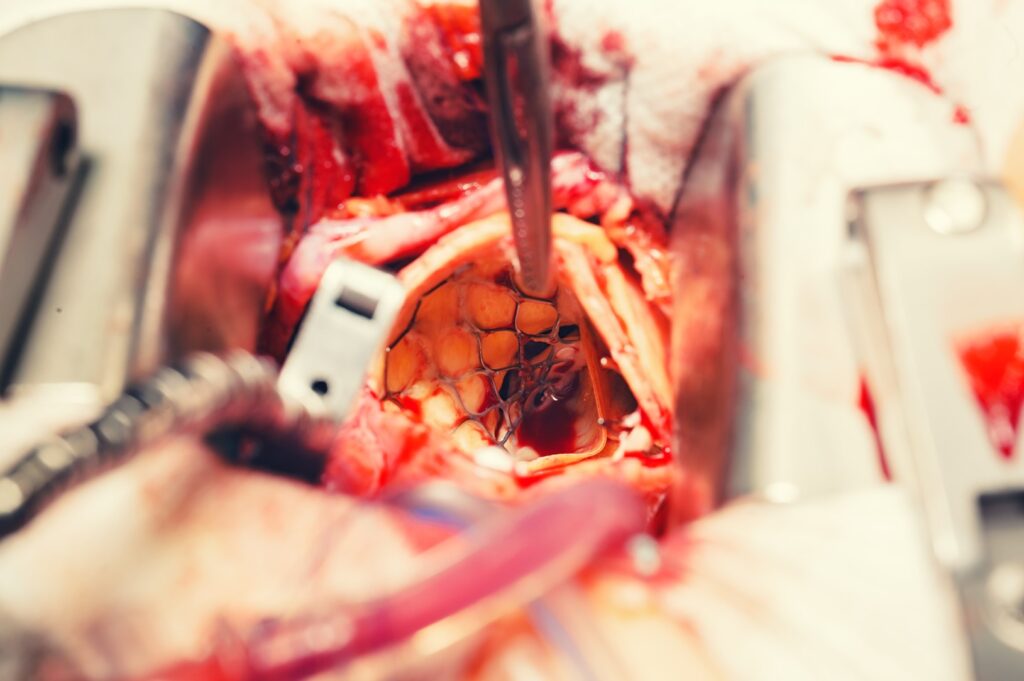

Transcatheter Aortic Valve Replacement (TAVR) is a minimally invasive surgical procedure used to treat aortic valve disease. It involves inserting a new heart valve through a small incision, typically in the groin, and guiding it up to the heart using a catheter. Once in place, the new valve is expanded and secured within the existing aortic valve, effectively replacing it.

TAVR is an alternative to traditional open-heart surgery and is generally used for patients who are considered high-risk or inoperable for conventional surgery. The procedure has shown promising results in improving symptoms and quality of life for patients with aortic valve disease.

TAVR vs Open Heart Surgery

| Transcatheter Aortic Valve Replacement (TAVR) | Open Heart Surgery |

| TAVR is a minimally invasive procedure that involves inserting a new valve through a catheter, typically in the groin, and threading it up to the heart. Once in place, the new valve is expanded and secured within the existing aortic valve, effectively replacing it. TAVR is generally used for patients who are considered high-risk or inoperable for traditional open-heart surgery. | Open Heart Surgery is a more invasive procedure that involves making a large incision in the chest and opening up the chest to access the heart. During this procedure, the heart is stopped, and the patient is connected to a heart-lung bypass machine, which keeps the blood circulating during the surgery. The surgeon then removes the diseased valve and replaces it with a new valve. |

Transcatheter Aortic Valve Replacement (TAVR) is a minimally invasive procedure that has revolutionized the treatment of aortic valve disease, especially in patients who are considered high-risk or inoperable for traditional open-heart surgery. TAVR involves inserting a new valve through a catheter and placing it within the existing aortic valve, which can improve symptoms and overall quality of life. While TAVR is not suitable for all patients, it has shown promising results and continues to evolve as a safe and effective treatment option for aortic valve disease.